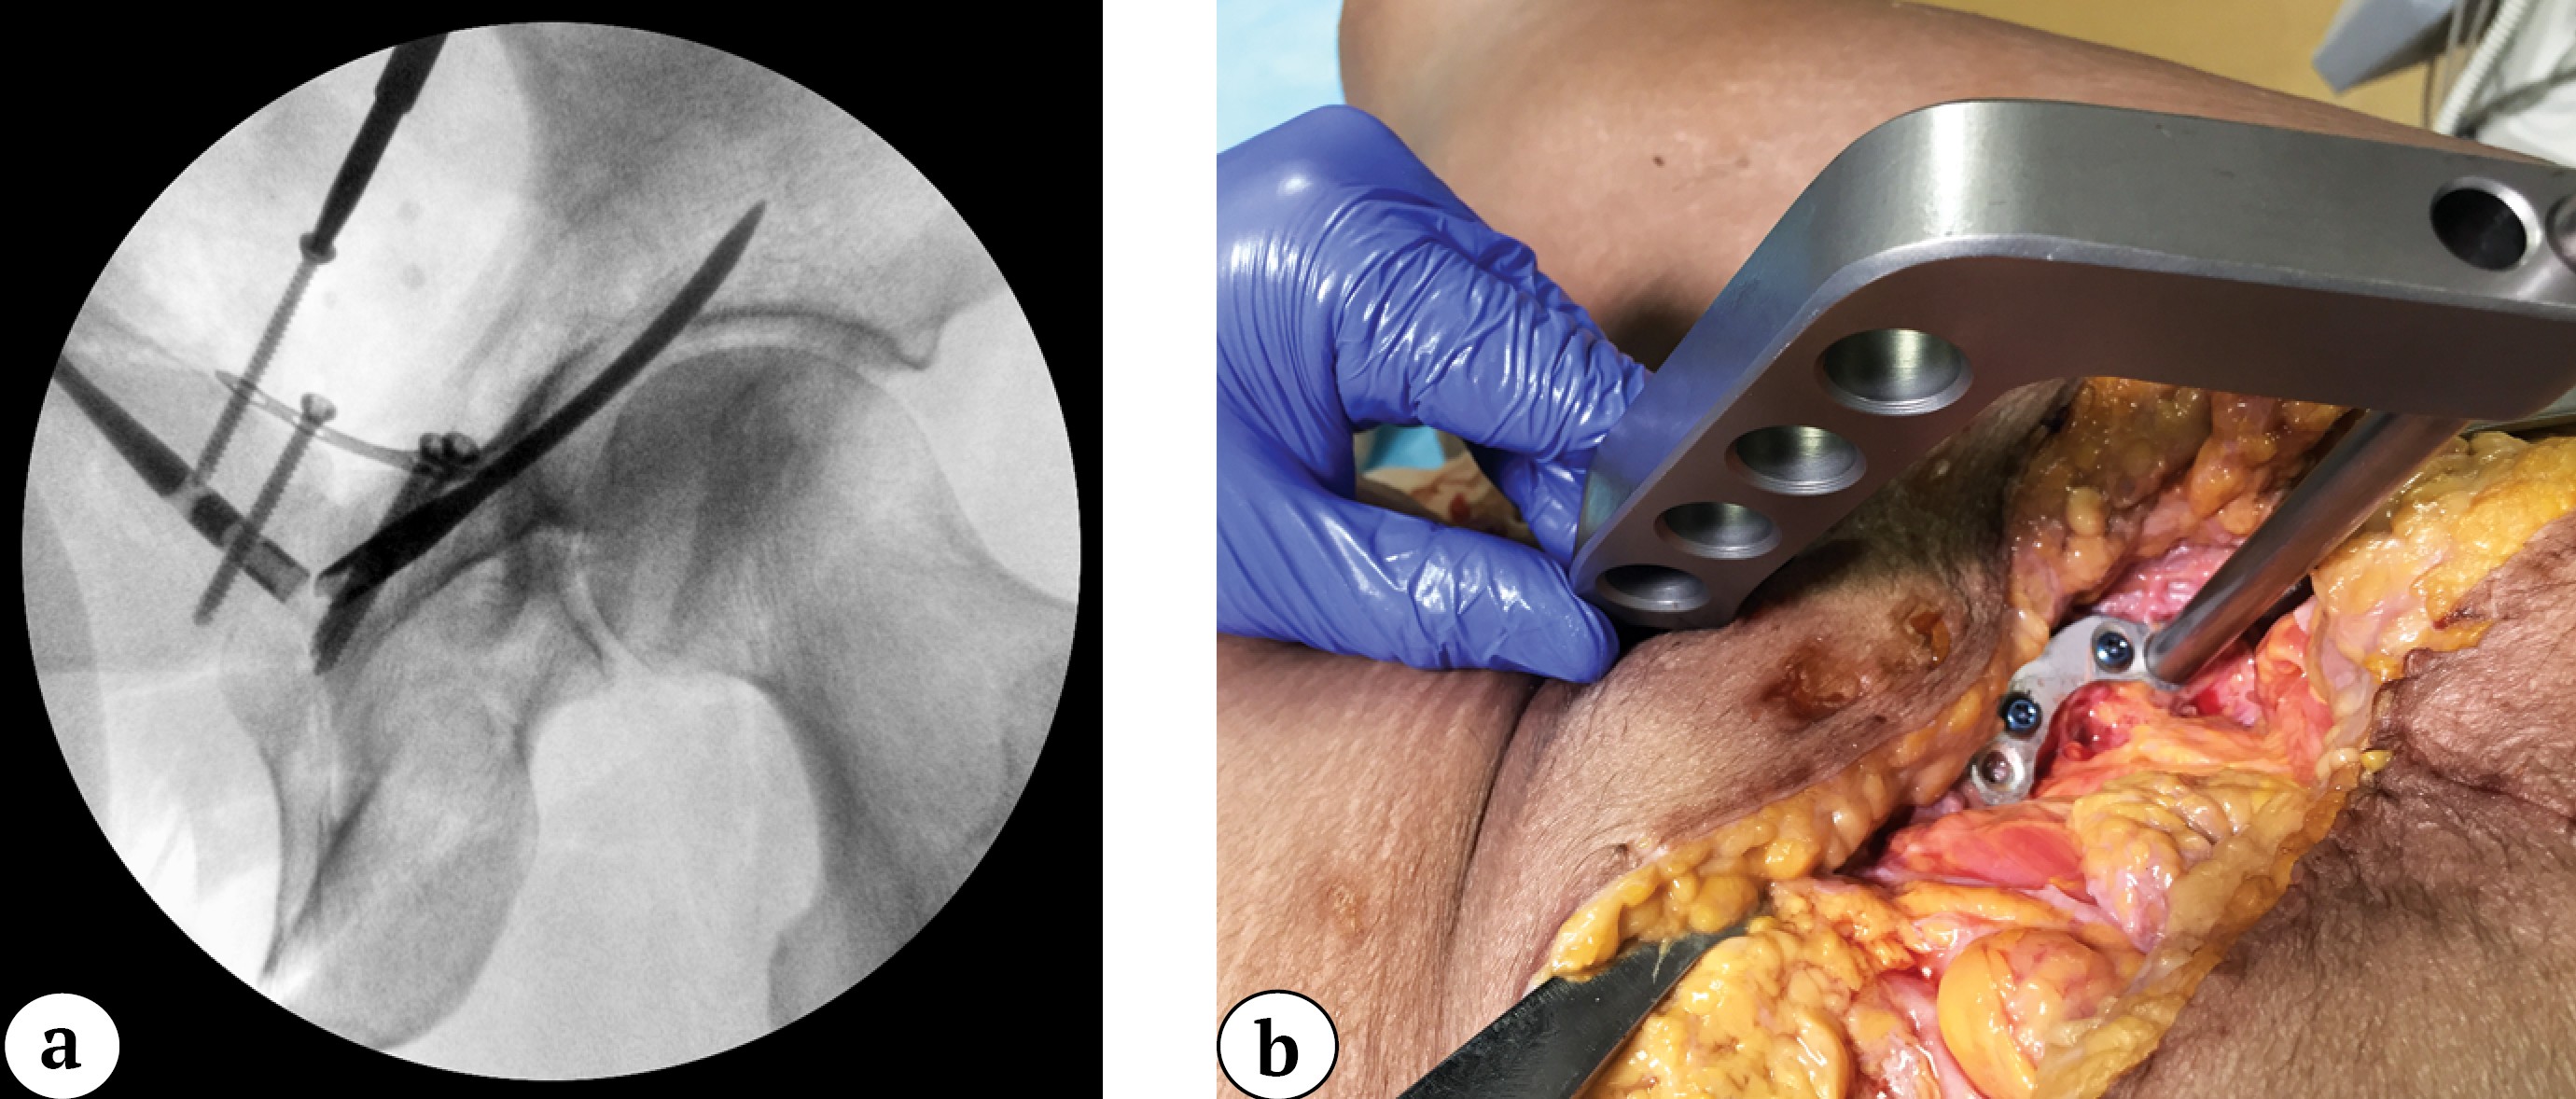

If necessary, the nail was slightly adjusted in a retrograde or antegrade direction to achieve precise alignment of the drill sleeve with the plate hole. The nail was then locked with two 3.5-mm cortical screws through the plate holes (Figure 5). The guide was removed and attached to the second nail (the ends of the nails usually protrude 1-2 mm from the entry points and are easily palpable). The optimal angle of the guide for subsequent nail locking was achieved by rotating it around the nail axis under C-arm control.

Figure 5. Intraoperative obturator-outlet view of the pelvis during locking of the nail with a 3.5-mm screw through the plate hole (a); intraoperative photograph of the surgical site showing interlocking of the second nail through the plate hole (b)